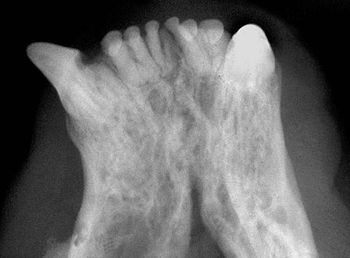

Intraoral radiography can help identify this pathology in your patients-and guide you toward the next step in your treatment plan.